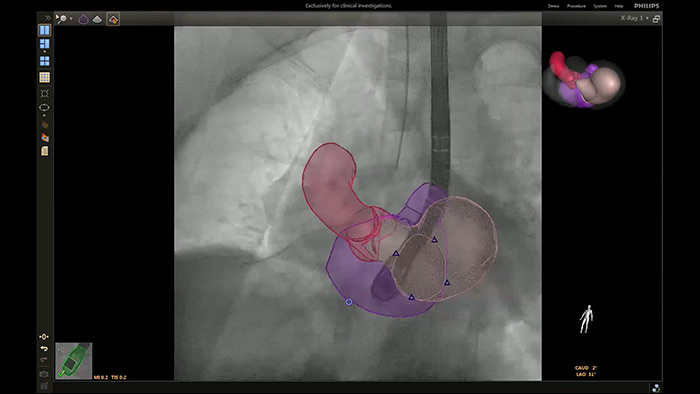

Superposition ETO 3D temps réel du déploiement de l’occlusion de l’appendice auriculaire gauche avec EchoNavigator

Segmentation de modèle 3D EchoNavigator

Guidage de ponction transseptale à l’aide d’EchoNavigator

Optimisation de la vue de la valve mitrale avec les modèles cardiaques EchoNavigator

Visualisation des valves mitrale et aortique avec les modèles cardiaques EchoNavigator